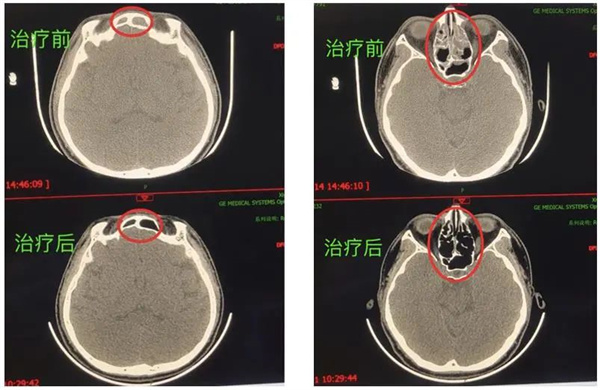

圖14.精準(zhǔn)電針刺激翼腭窩區(qū)治療前后示例圖